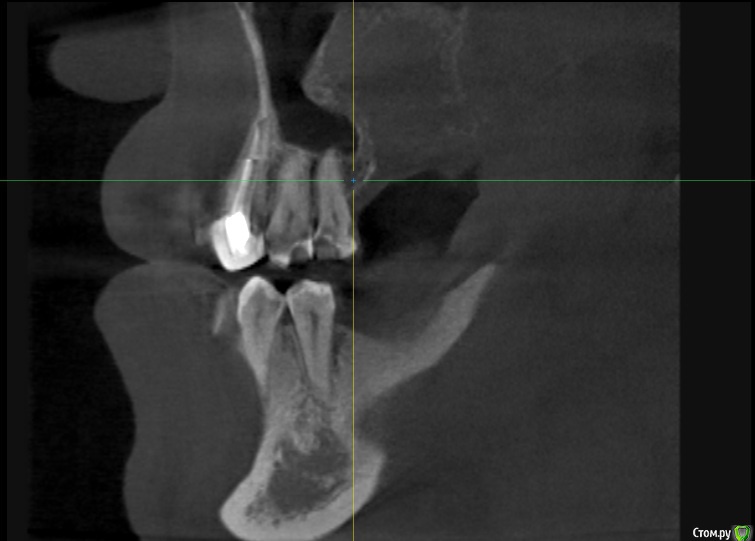

alboard Опубликовано 9 марта, 2017 Поделиться Опубликовано 9 марта, 2017 В области 16,17,18 дно отсутствует. Какая здесь может быть тактика? Ссылка на комментарий

Dok22 Опубликовано 9 марта, 2017 Поделиться Опубликовано 9 марта, 2017 В пазухе какое то образование. 1 Ссылка на комментарий

mr.Fog Опубликовано 9 марта, 2017 Поделиться Опубликовано 9 марта, 2017 Скорее всего это кальцифицированные останки радикулярной кисты. Ссылка на комментарий

Oscar Опубликовано 9 марта, 2017 Поделиться Опубликовано 9 марта, 2017 давно зубы удалены? Похоже на ретенционную кисту пазухи... Можно попробовать отслоить шнайдер снизу, если перфорация выход только "парашют"... Ссылка на комментарий

drpetrovich Опубликовано 13 марта, 2017 Поделиться Опубликовано 13 марта, 2017 Действительно по томограмме больше похоже на резидуальную кисту, т.е. при зондировании проваливаешься не в пазуху, а в полость кисты. Отделяемое было кстати? Вопрос про давность удаления актуален. Ссылка на комментарий